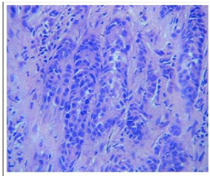

Figure 2 Histopathological reporting- Metastatic deposits of Adenocarcinoma? Primary.

The patient was undertaken for Contrast MRI to rule out the abscess MRI was performed at 3-T (ACHIEVA, Philips Medical Solutions) including T1-weighted, axial T2-weighted, coronal T1-weighted, and sagittal T2-weighted turbo spin echoes and coronal Short Tau Inversion Recovery (STIR) sequences. A soft tissue lesion measuring 9.8 x 5.9 x 9.5 cm was seen in left Gluteus Maximus muscle with mild surrounding oedema and heterogeneous enhancement with non-enhancing areas on post contrast images. Neurovascular bundle was intact. Incidentally, similar appearing lesion measuring 19 x 25 x25mm is also seen in right Gluteus Medius muscle (Figures 1a&1b). There was no haemorrhage or calcification within the lesion. A provisional diagnosis of neoplastic aetiology was considered. For confirmation, Ultrasound-guided biopsy was performed which confirmed the features of metastasis from esophageal adenocarcinoma. Sections from Tru­cut biopsy showed malignant tumor arranged to form sheets, islands and cords of tumor cells which were round to oval with plemorphic, hyperchromatic nuclei and prominent nucleoli. Cytoplasm was moderate and pale. Tumor was seen to be infiltrating the fibrous stroma, Occasional mitotic figures were also seen along with large area of necrosis (Figure 2). The patient was eventually managed with chemotherapy for muscle metastasis.